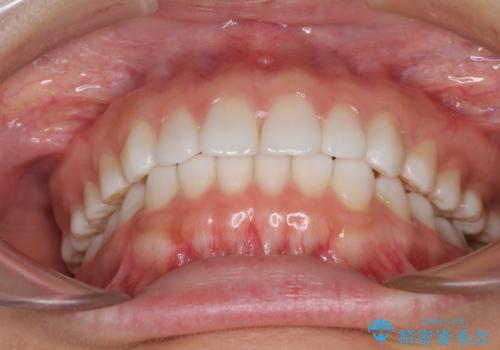

インビザラインによる軽度な出っ歯の矯正治療

- 上の前歯の出っ歯を治したいとのことで来院された患者様です。

上下顎ともにIPR(歯と歯の間を削る)と歯列全体の拡大によって口元が引っ込むように設計し、インビザラインにより治療を行うこととしました。

どこまで口元を引っ込めることができるのか、患者様自身も正直分からない部分があったため、少しずつ治療ゴールを変更しながら仕上げていきました。

気になっていた前歯の飛び出した印象は、最終的にはスッキリと引っ込み、大変満足していただきました。